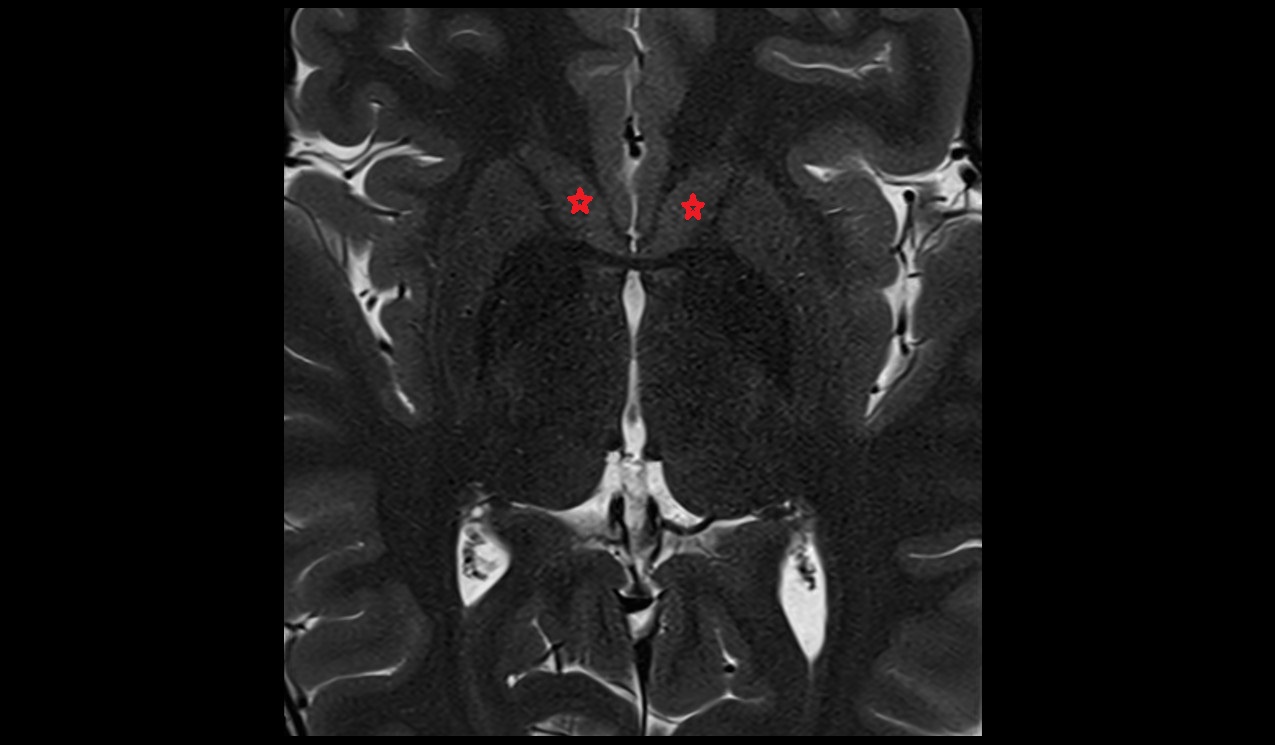

- Hippocampal body

- Hippocampal head

- Hippocampal tail

- Body of hippocampus

- Head of hippocampus

- Tail of hippocampus

- Hippocampus